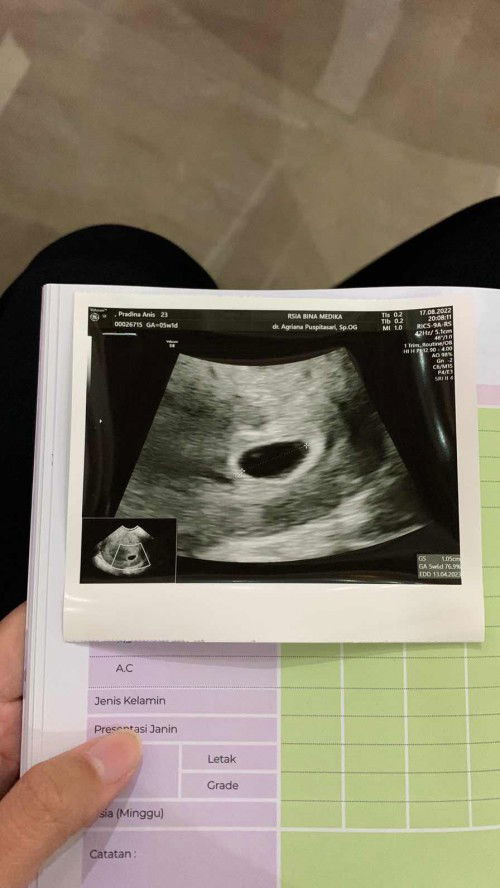

USG Transvaginal